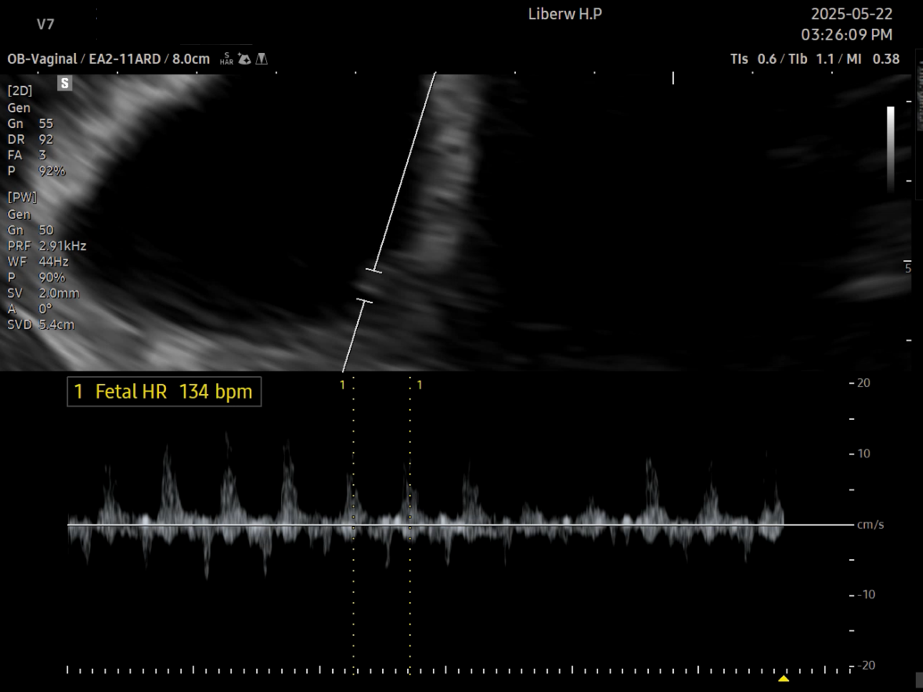

콩알보다도 작은 심장이 콩딱거리며 뛰는 모습이라니, 너무 작고 소중하다. 임신 소식을 처음 알게 되었을 때와는 또 다른 감동이다. 이번에도 역시 <감사합니다>라며 감탄을 연발했다. 나의 심장은 <쿵- 쿵-> 심박수는 77 정도였는데, <콩딱콩딱> 뛰는 아가의 심박수는 무려 134. 두 배나 빠르게 뛴다. 빠른 심장박동은 잘 자라고 있다는 증거라니, 감사하다는 말이 절로 나온다.

나의 맥박수는 77, 아기의 맥박수는 134!